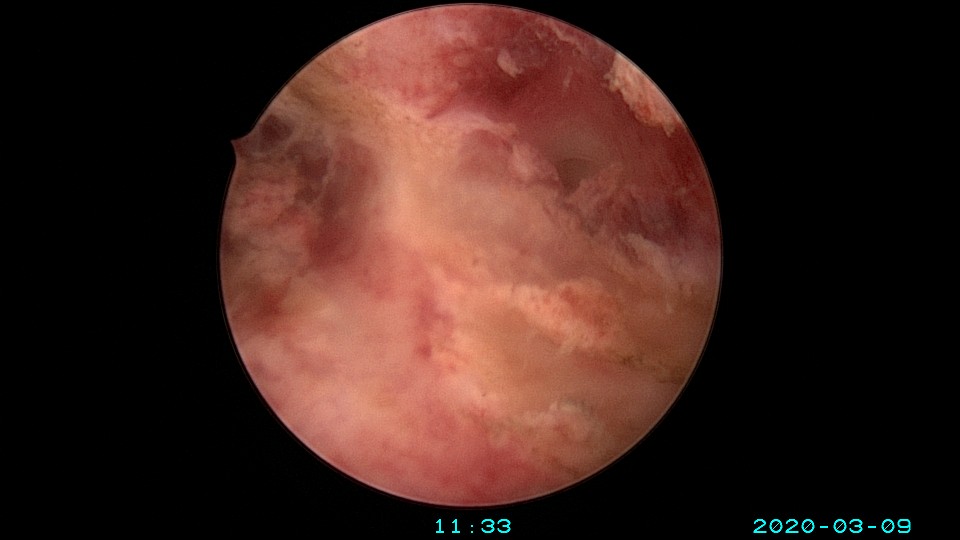

患者36岁,G3P0,自然流产3次,发现宫腔粘连3个月。2020年3月宫腔镜探查,子宫前倾后屈位,宫深8.5cm,宫颈管粘连狭窄,扩宫进入宫腔,见宫腔中下段两侧壁粘连,剪刀及双极电切分粘,宫腔形态恢复正常,双侧输卵管开口显露。2020年4月宫腔镜二探取球囊,宫腔形态正常,双侧输卵管开口可见。2021年6月自然妊娠,2022年2月足月剖宫产分娩。现42岁,G4P1。